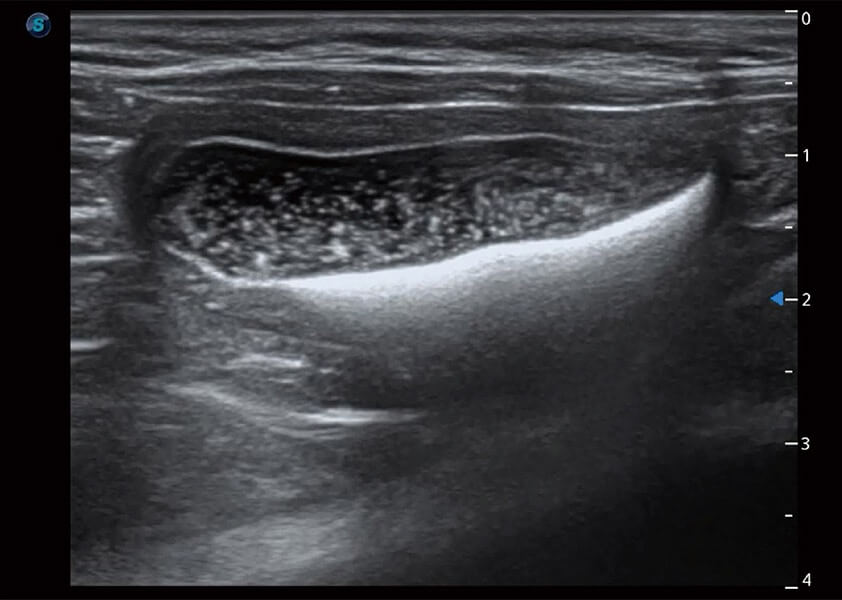

ProPet 60 作為一款高端臺(tái)式動(dòng)物超聲設(shè)備,為動(dòng)物醫(yī)生的日常診斷提供了一系列貼合動(dòng)物臨床需求、解決臨床實(shí)際問題的高級成像功能。憑借全系列高清探頭,滿足醫(yī)生對腹部、心臟、生殖、淺表、肌骨等成像的所有需求,切實(shí)幫助您提升檢查效率,提高診斷信心。